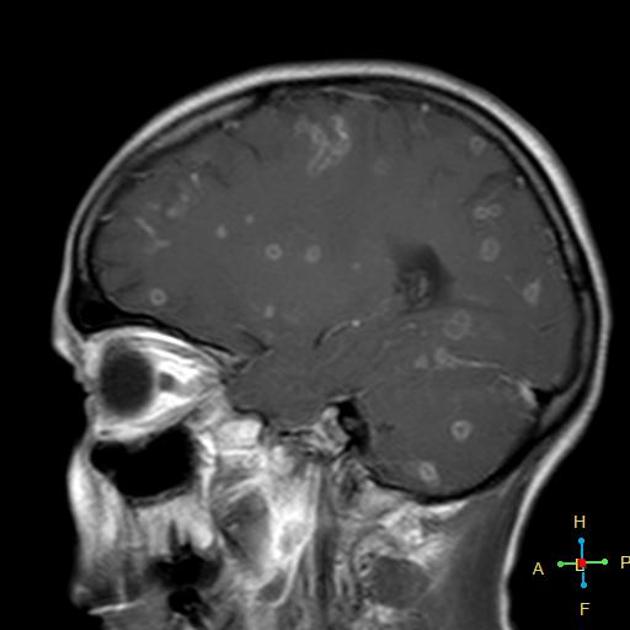

Лептоменингеальная опухоль: диагностика и лечение